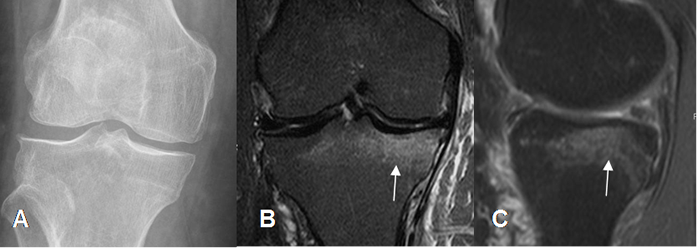

Fig 37. Contusión osea.

A: Rx AP. No se aprecian signos de lesión traumática.

B: RM coronal y C: RM sagital en STIR. Contusión osea en la parte postero-superior del platillo tibial medial.